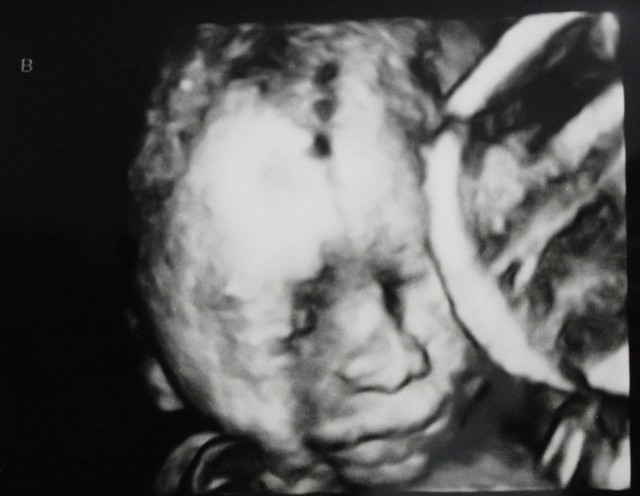

但這次有點不同的是,先進來做檢查的是一位小姐,而且她還看了蠻久的

我跟老公最注意的應該就只有螢幕上顯示出胎兒大小

看到兩個都有1500以上,感覺還蠻開心的

直到那位測試員跟在隔壁看另一個人的我的主治醫師說:「醫師,跟剛剛的雙胞胎一樣」

操作員指著螢幕上的某個點,主治醫師則面色凝重

沒多久,醫生說:「右邊的這個因為自己的臍帶打結,養分無法通過而沒心跳了!」